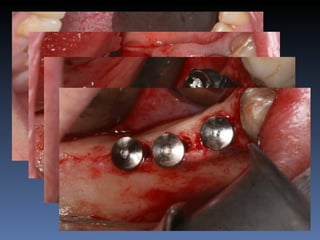

BOX 3

Plano de tratamento: Reabilitação bilateral posterior

mandibular com instalação de 6 implantes endo-

ósseos, para reabilitação protética fixa.

Zona 4.4, 4.5, 4.6   Zona 3.5, 3.6, 3.7